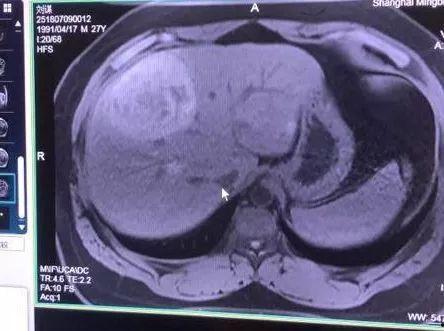

首先,咱们得弄清楚肝癌和吃瓜之间的关系。肝癌,顾名思义,就是肝脏出了问题。而吃瓜,顾名思义,就是吃西瓜。那么,这两者之间有什么联系呢?

据《中国肝癌防治指南》指出,肝癌的发生与多种因素有关,包括病毒性肝炎、酒精性肝病、非酒精性脂肪性肝病等。而西瓜,作为一种富含水分和维生素的水果,对肝脏有一定的保护作用。但是,这并不意味着肝癌患者就可以肆无忌惮地吃瓜。